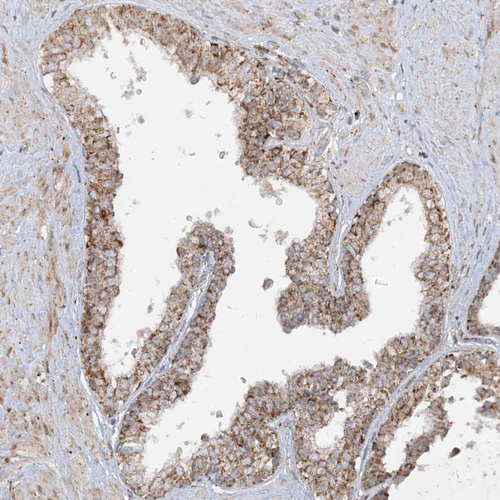

Immunohistochemical staining of human fallopian tube, kidney, prostate and testis using Anti-NDUFAF3 antibody HPA035377 (A) shows similar protein distribution across tissues to independent antibody HPA035376 (B).